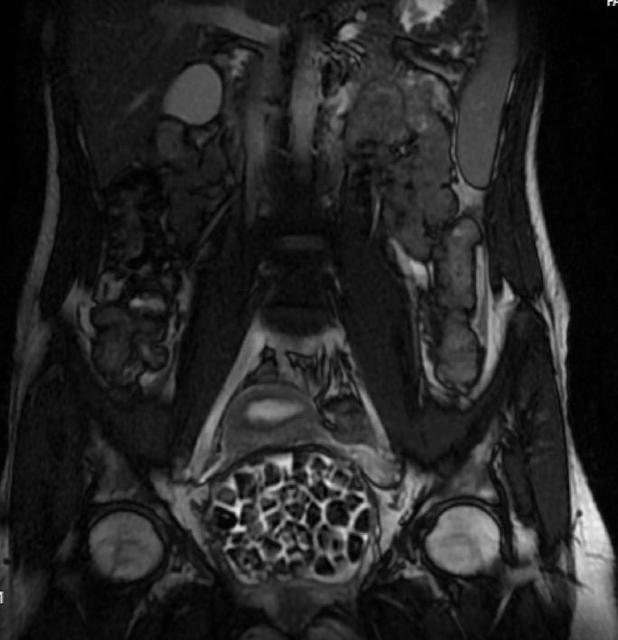

Doğumsal ürolojik hastalıkla dünyaya gelen 21 yaşındaki Fatma Nur Öztürk, şiddetli karın ağrısı şikayetiyle hastaneye gitti, yapılan operasyonla vücudundan 287 adet taş çıkarıldı. Taşlar hem sağlık ekibini hem hasta ve ailesini şok ederken uzmanlar, "Mesaneden vajene ... haberin devamı için tıklayın

VÜCUDUNDAN 287 TANE TAŞ ÇIKARILDI, DOKTORLAR BİLE ŞOK OLDU: "LİTERATÜRDE ÇOK NADİR GÖRÜLEN BİR OLAY" KARIN AĞRISIYLA DOKTORA GİTTİ, VÜCUDUNDAN 287 TANE TAŞ ÇIKARILDI UZMANLAR: "BİZ DE O KADAR TAŞ BEKLEMİYORDUK, ÇOK ŞAŞIRDIK"